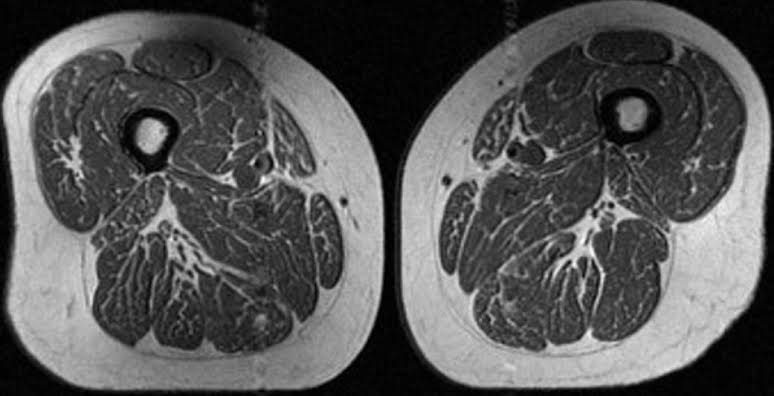

Diets high in ultraprocessed foods create streaks of fat in human muscles that may lead to osteoporosis, a new study found.